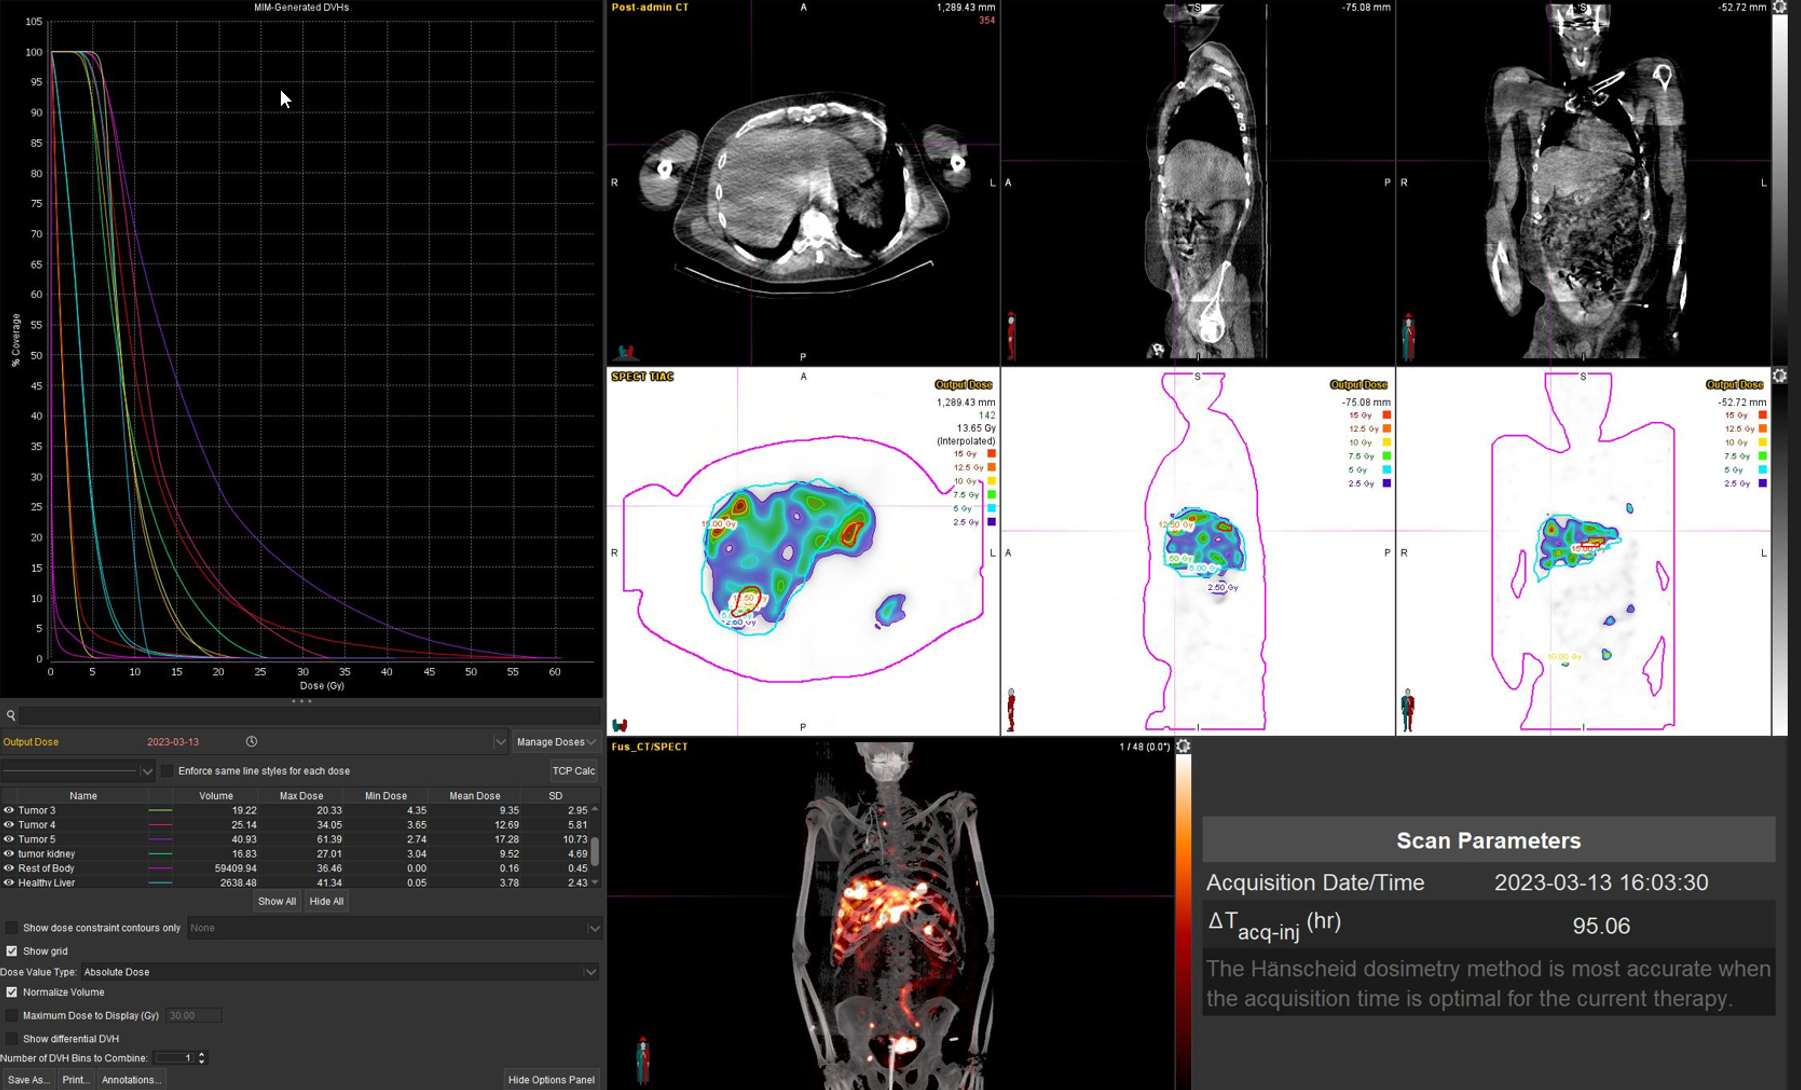

Η θεραπεία με Lu-177 DOTATATE (PRRT – Peptide Receptor Radionuclide Therapy) αποτελεί μια από τις πλέον εξελιγμένες μορφές στοχευμένης ραδιονουκλιδικής θεραπείας για νευροενδοκρινείς όγκους του γαστρεντερικού και του παγκρέατος, αξιοποιώντας την υπερέκφραση των υποδοχέων σωματοστατίνης στους νεοπλασματικούς ιστούς. Η διαδικασία περιλαμβάνει τον ακριβή προσδιορισμό της έκτασης της νόσου μέσω Ga68 DOTATATE PET/CT, την επιβεβαίωση υψηλής έκφρασης υποδοχέων SSTR και στη συνέχεια τη χορήγηση του Λουτέσιο-177 DOTATATE, το οποίο δεσμεύεται εκλεκτικά στους ανωτέρω υποδοχείς. Η ενέργεια του β-εκπομπού Λουτέσιου επιτρέπει στοχευμένη κυτταροτοξική δράση μέσα στον όγκο, με ελάχιστη διασπορά σε υγιείς ιστούς. Η σύγχρονη πρακτική ενσωματώνει ειδικά λογισμικά δοσιμετρίας, που υπολογίζουν την απορροφούμενη δόση σε κρίσιμα όργανα (ήπαρ, νεφροί, μυελός) και την πραγματική δόση στον όγκο, επιτρέποντας εξατομικευμένο σχεδιασμό και βελτιστοποιημένη θεραπευτική στρατηγική. Μετά από κάθε κύκλο θεραπείας πραγματοποιείται απεικονιστικός έλεγχος, αξιολόγηση τοξικοτήτων και συνολική εκτίμηση ανταπόκρισης, καθοδηγώντας τις επόμενες φάσεις της θεραπείας. Το Lu-177 DOTATATE έχει αποδειχθεί εξαιρετικά αποτελεσματικό στη σταθεροποίηση και συχνά στη συρρίκνωση της νόσου, παρατείνοντας την επιβίωση και βελτιώνοντας σημαντικά την ποιότητα ζωής των ασθενών.